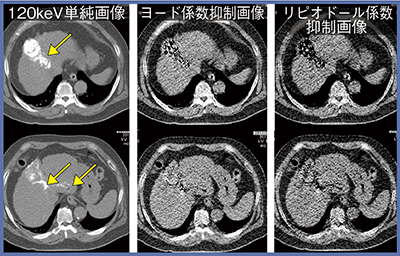

東芝メディカルシステムズのDECTは,閾値の設定を変えて,リピオドールとヨード造影剤の弁別を行うことができる。Leeらは,TACE後にリピオドールの沈着があった患者に対してDECTを施行し,肝実質,viable HCC,大動脈をcolor-coded iodine CTのウインドウ幅としてヨード造影剤の造影される範囲との閾値に設定することで,造影効果の区別が可能になったと報告した1)。当院でも同様の検討を行ったところ,閾値を設定したリピオドール抑制画像では,一部分のヨード造影剤も抑制されてしまっている(図4)。DECTでは適切な閾値の設定は必要であるが,それだけでは物質の弁別は限定的であるという結果となった。

図4 閾値を設定したリピオドールとヨード造影剤の弁別